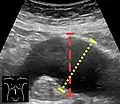

Ultrasonography in the sagittal plane, showing axial plane measure (dashed red line), as well as maximal diameter (dotted yellow line), which is preferred